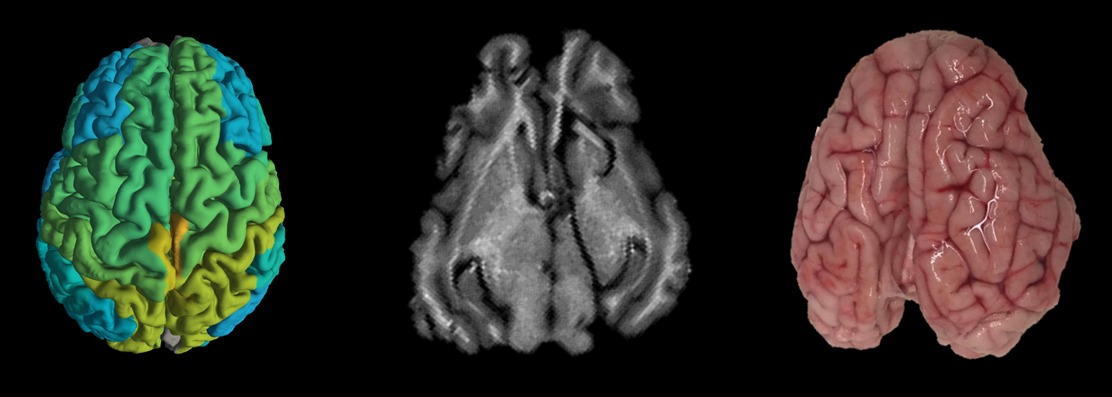

In July 2019 a paper was published in Nature Communications, Professor Aviv Mezer and his team at the Hebrew University of Jerusalem (HUJI)’s Edmond and Lily Safra Center for Brain Sciences successfully transformed an MRI from a diagnostic camera that takes into a device that can record changes in the biological makeup of brain tissue. This is especially important for doctors looking to understand whether a patient is merely getting older or developing a neurodegenerative disease, such as Alzheimer’s or Parkinson’s.

“Instead of images, our quantitative MRI model provides molecular information about the brain tissue we’re studying. This could allow doctors to compare brain scans taken over time from the same patient, and to differentiate between healthy and diseased brain tissue, without resorting to invasive or dangerous procedures, such as brain tissue biopsies,” explained Mezer.

Whereas current MRI scans provide only pictures of the human brain, this new technique provides biological readouts of brain tissue—the ability to see what’s going on on a molecular level, and to direct a course of treatment accordingly. “When we take a blood test, it shows us the exact number of white blood cells in our body and whether that number is higher than normal due to illness. MRI scans provide images of the brain but don’t show changes in the composition of the human brain, changes that could potentially differentiate normal aging from the beginnings of Alzheimer’s or Parkinson’s,” shared PhD student Shir Filo who worked on the study.